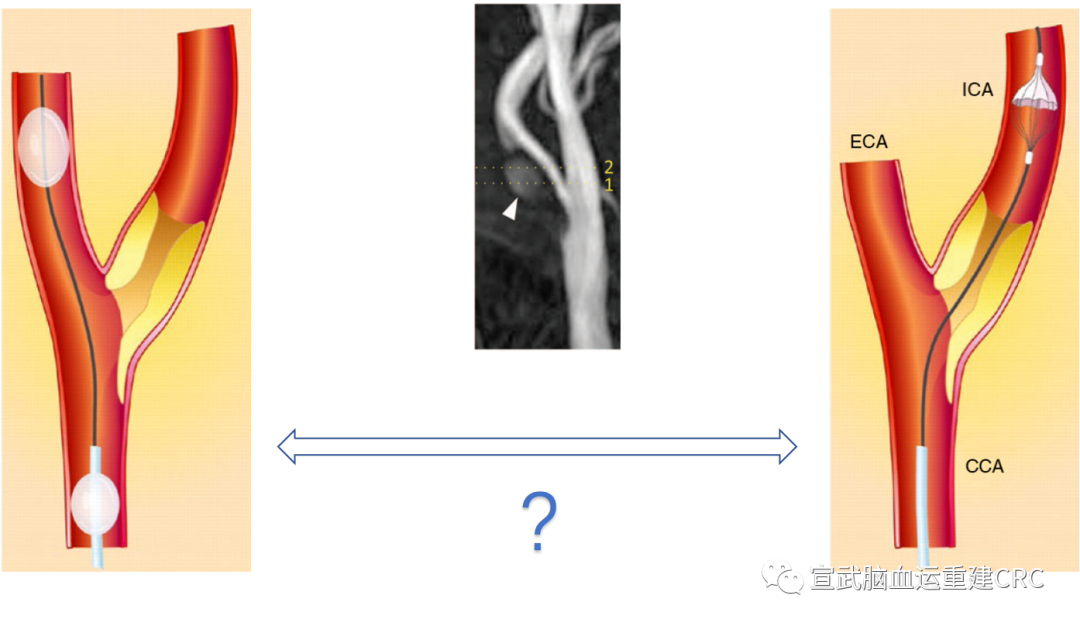

市面上的栓塞保护装置最主要的三种设计原理:

1、保护伞

2、远端的球囊

3、近端结合颈总的球囊和颈外的球囊来阻断血流

保护装置的选择尚无推荐

从上面的研究可以发现,保护装置的选择并没有一个定论,证据是不足的。需要我们去提供新的证据,于是我们决定去设计一个试验,在有高危的斑块的病人人群里,去选择栓塞保护装置。

高危斑块CAS栓塞保护装置如何选择?

研究设计

从朴素的角度,选择两种不同的栓塞保护装置,他们的原理不一样,远端的保护伞有他的问题,要先通过斑块再打开保护装置。但是近端的球囊MoMa的这个装置我们可以在不干扰斑块的情况下,阻断血流从根本上去解决这个问题。

于是我们就有一个假设,认为MoMa这个装置近端的保护装置的保护效力,要比远端的保护装置更好。就把MoMa选作为一个试验组,干预组。以Spider为代表的这种保护伞,定为一个对照组。